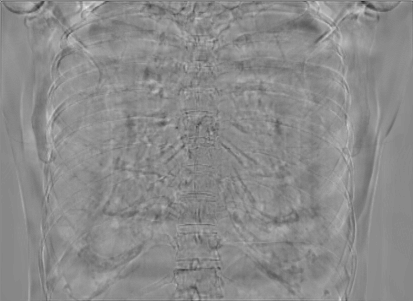

5.1 Chest Data

Figure 10: Perspective deformation learning in one exemplary patient case for chest X-ray imaging. The maximal horizontal cardiac diameter and the maximal horizontal thoracic diameter in (b) and (d)-(f) are indicated by the horizontal red lines, while those in the reference image (a) are green lines. The cardiothoracic ratio, RMSE, and SSIM for each image is displayed in its corresponding subcaption.

The results of one patient in chest X-ray imaging are displayed in Fig. 10, where the cardiothoracic ratio is assessed as an exemplary clinical application [32]. In the reference image (Fig. 10(a)), the maximal horizontal cardiac diameter (MHCD) and the maximal horizontal thoracic diameter (MHTD) are indicated by two green horizontal lines. Its cardiothoracic ratio is 0.4237. In the 0superscript00^{\circ} perspective projection image (Fig. 10(b)), all the anatomical structures can be visualized with fine resolution. However, due to perspective deformation, anatomical structures, e.g. the ribs and the spine, are deformed. The deformations are visualized better in the difference image Fig. 10(c). Compared with the ribs and the spine, the heart has less deformation as its location is closer to the isocenter. In Fig. 10(b), the MHCD and the MHTD are indicated by two red horizontal lines, while the green lines are those of the reference image. While the MHCD has changed little from 10.47 cm to 10.16 cm, the MHTD has changed considerably from 24.71 cm to 25.40 cm. As a consequence, the cardiothoracic ratio becomes 0.4002, which is below the normal range of 0.42 - 0.50 [32]. The result of learning perspective deformation from 0superscript00^{\circ} single view is displayed in Fig. 10(d), where the MHCD and the MHTD are 10.63 cm and 24.71 cm, respectively. The MHTD of Fig. 10(d) is the same as that of the reference image. This is also reflected by the difference image Fig. 10(g), where the lower ribs have small errors. However, the upper ribs as well as the spine still have considerable errors. The results of perspective deformation learning from 0&180superscript0superscript1800^{\circ}\&180^{\circ} views in Cartesian and polar coordinates are displayed in Fig. 10(e) and Fig. 10(f), respectively. The measured MHCDs and MHTDs in these two images are very close to the reference ones. Hence, their cardiothoracic ratios, 0.4214 and 0.4240 respectively, are close to the reference ratio as well. In the difference images (Fig. 10(h) and Fig. 10(i)), the errors of ribs and spine decrease as their boundaries are no longer apparently visible. Nevertheless, Fig. 10(i) has less error than Fig. 10(h), achieving the smallest RMSE value of 3.83. The quantitative evaluation of all the 162 testing datasets is displayed in Tab. II, where learning perspective deformation from two complementary views in polar coordinates achieves the least RMSE 4.98 and highest SSIM 0.9517, demonstrating the superiority of learning perspective deformation from two complementary views in polar coordinates.